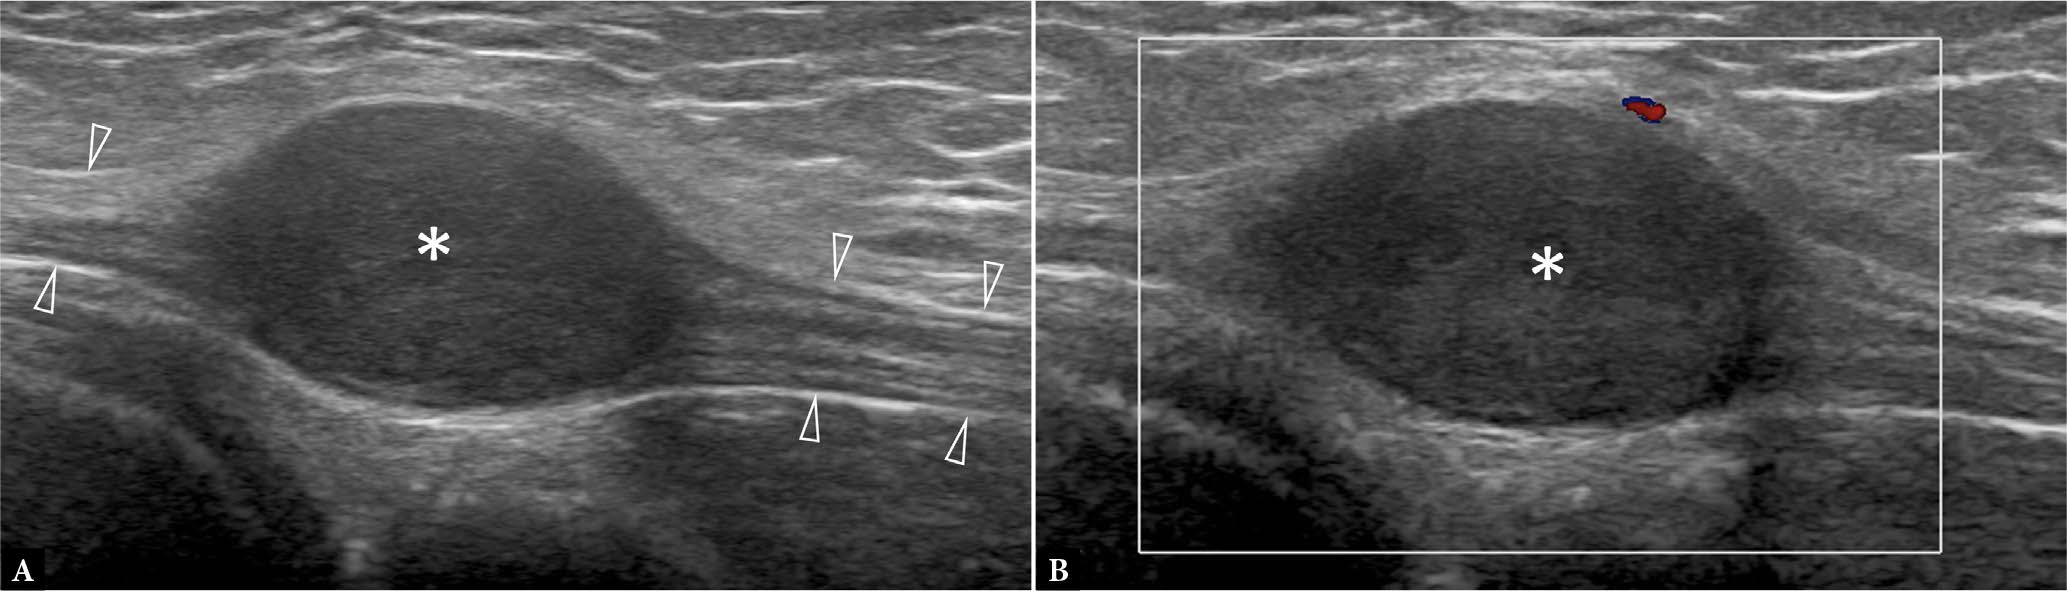

Fig. 1.

63-year-old male with enlarging thigh mass for five months. Transverse A. greyscale and B. color Doppler ultrasound show large moderately hyperemic mass (arrows) partially encasing the femoral (F) cortex. The large size, rapid growth, and moderate hyperemia make sarcoma most likely. No necrosis is evident. C. Axial proton-density weighted image shows that the tumor contacts, but does not infiltrate, the femoral cortex. The femoral neurovascular bundle (NVB) is also not infiltrated (arrowhead). T1-weighed fat-saturated post-contrast D. axial and E. sagittal images show that the central tumor area (*) is non-enhancing, compatible with necrosis. The necrosis cannot be appreciated on ultrasound A., B. Percutaneous biopsy of the tumor margins revealed a pleomorphic rhabdomyosarcoma